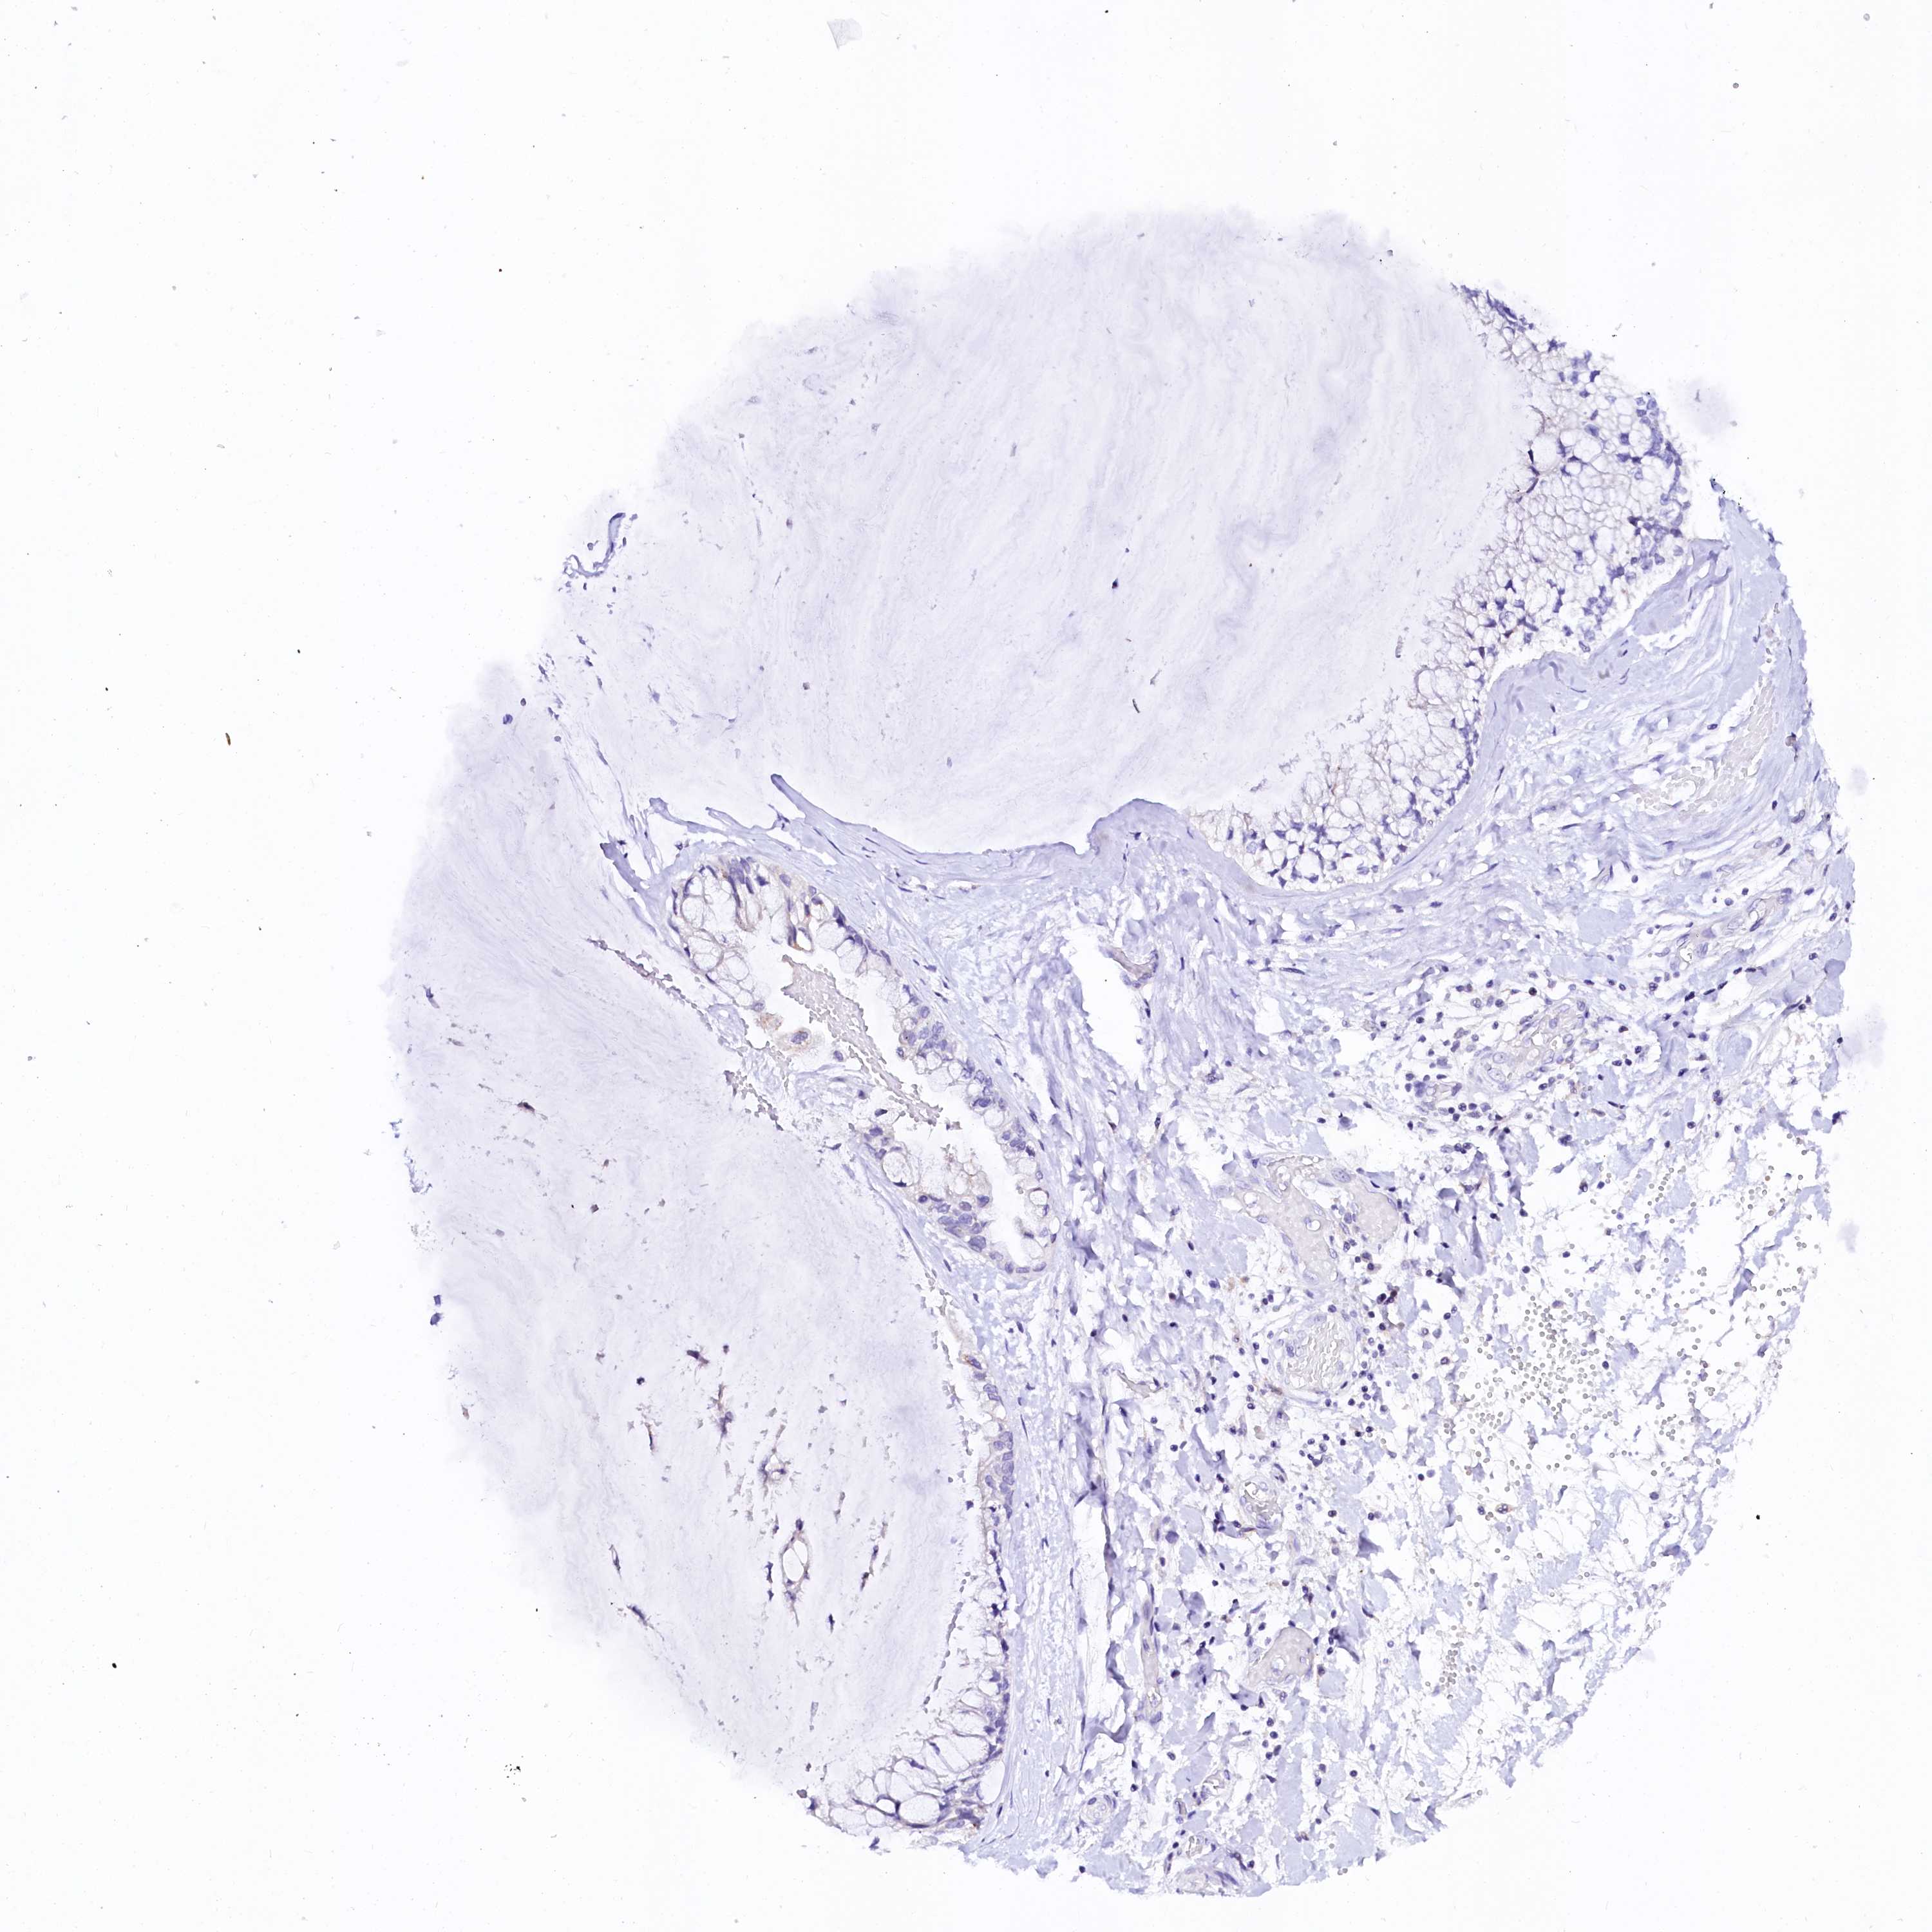

OVARIAN CANCER - Protein expressioni

A mouse-over function shows sample information and annotation data. Click on an image to view it in a full screen mode. Samples can be filtered based on level of antibody staining by selecting one or several of the following categories: high, medium, low and not detected. The assay and annotation is described here.

Note that samples used for immunohistochemistry by the Human Protein Atlas do not correspond to samples in the TCGA dataset.

Antibody stainingi

Antibody staining in the annotated cell types in the current human tissue is reported as not detected, low, medium, or high, based on conventional immunohistochemistry profiling in selected tissues. This score is based on the combination of the staining intensity and fraction of stained cells.

Each image is clickable and will lead to virtual microscopy that enables deeper exploration of all samples and also displays staining intensity scores, fraction scores and subcellular localization as well as patient and tissue information for each sample.

Antibody HPA039453

Cystadenocarcinoma, serous, NOS

Carcinoma, endometroid

Cystadenocarcinoma, mucinous, NOS

Carcinoma, NOS